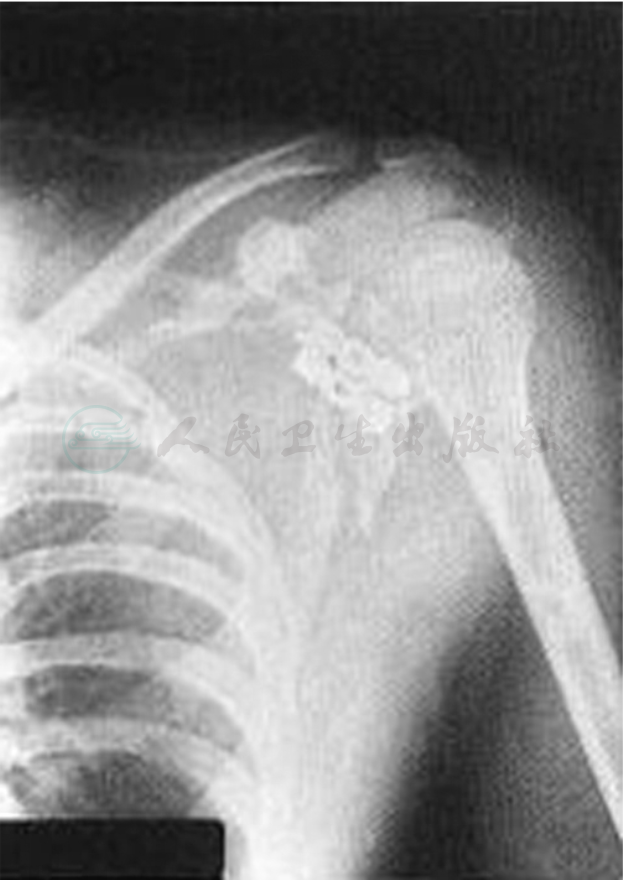

影像学检查可以明确诊断。前后正位和经腋窝轴位X线片可以诊断出大多数喙突骨折,但由于其他结构的重叠影响,可以借助CT检查帮助诊断;进一步影像学检查在某些情况下也很有用,如斜位像可以看清楚肩胛骨骨折的骨折线,45°尾侧倾斜像有助于确认锁骨骨折,45°头侧倾斜位摄片,可清楚显示喙突的投影(图1)。腋位X线检查对诊断喙突骨折也很有价值。另外,怀疑有喙突骨折时可以拍双侧上肢带骨的垂直应力位X线片,也能发现喙突的位置失常,协助诊断。

图1 喙突45°头侧倾斜像

适用于特殊人群,或骨折延伸至基底部或关节盂的骨折和陈旧性骨折有明显症状者。对于运动员来讲,则建议其考虑手术内固定治疗,特别是从事以上肢频繁活动为主手工劳动者。早期失治的病例,如晚期残留有疼痛症状,若位于喙突基底部骨折,骨块较大,可考虑修整骨折端面后复位骨折,可吸收松质骨螺钉内固定;若骨折处于喙突尖部,骨折块较小,难以复位内固定,可行喙突远端切除、联合肌腱再种植固定术。陈旧性骨折除了必须有良好的复位和固定外,为确保骨折愈合,骨折端周围植骨是一个重要环节。内固定主要方法是骨折端复位后应用松质骨螺钉自喙突尖部向基底部方向拧入固定,有的患者为了避免二次手术取出内固定螺钉,可选用国产或进口的可吸收螺钉内固定(图2)。

图2 喙突骨折内固定示意图